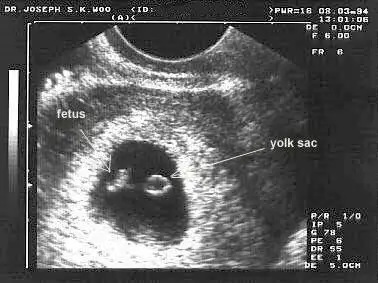

Seninkisi tek canim bak sana ornek bi ultrason atayim bana ait degil tek gebelik. Sende kese boslugu embriyo ve kordonu gorunuyor.

Eklentiler

• images (7).webp

17,5 KB · Görüntüleme: 66